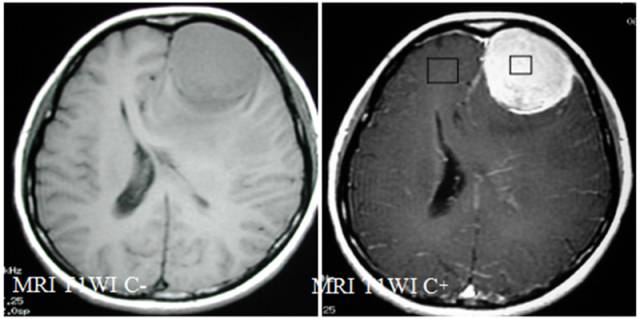

MR平扫病灶呈等信号,增强病灶呈较均匀强化;MRS病灶侧波谱显示Cho峰明显升高,Cr、NAA峰未显示,并见Glx、GSH峰和倒置的Ala峰。